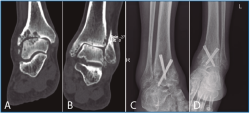

La segunda artrodesis se llevó a cabo durante el año siguiente a la primera intervención. La artrodesis fue tibioastragalina bilateral en 2 pacientes y tibiotalocalcánea (TTC) bilateral en el paciente restante. La estabilización ósea se realizó en un caso con 2 tornillos canulados Acutrak Plus® (Acumed, Hillsboro, EE. UU.) cruzados en ambos tobillos (Figura 1), en otro caso con clavo endomedular retrógrado T2 12 × 200 mm (Stryker, Schönkirchen, Alemania) en ambos tobillos (Figura 2) y en el último caso se utilizaron tornillos canulados Acutrak Plus® cruzados en el tobillo izquierdo y la técnica Putti en el tobillo derecho (Figura 3). La fijación de la artrodesis se realizó con el pie en plantígrado.

Figura 3. Caso 3. Varón de 77 años con artrosis bilateral de tobillo primaria. Radiografía lateral de tobillo derecho (A) y anteroposterior izquierdo (B) preoperatoria. Radiografía lateral de tobillo derecho que muestra una artrodesis tibioastragalina mediante técnica Putti con una consolidación parcial, asintomática, de la artrodesis y cambios degenerativos de la articulación subastragalina posterior pasados 21 meses de la intervención (C). En el tobillo izquierdo (D) se aprecia una artrodesis tibioastragalina mediante tornillos canulados cruzados del tobillo izquierdo con una consolidación parcial, asintomática, de la artrodesis al año y medio de la última intervención.